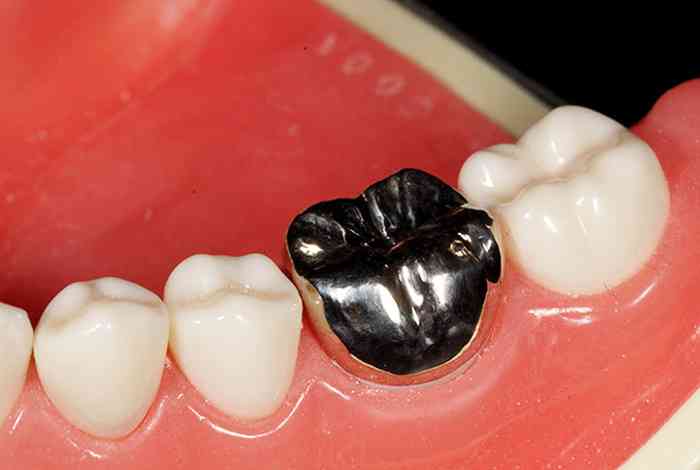

歯医者で歯を覆うように銀歯と言われました。

まだ結婚してないのに下の歯が銀歯だと印象良くないと思いますが、皆さんは見える銀歯はどうされましたか?セラミックにしたか銀歯にしたかなどお聞かせください。![銀歯は印象がマイナス?]()

22. 匿名 2024/04/04(木) 16:05:19

一番奥の下の歯は覆うように銀歯

やはり奥歯は圧力がかかるしセラミックより強度のある銀歯の方がいいとのことで

それ以外の見えるところは元々の銀歯も全てレジン?やセラミックに変えてくれた歯科医の言うことなのですんなり受け入れた+81